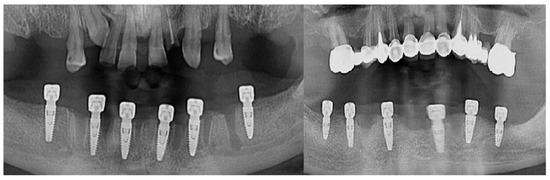

In the lateral areas of the jaws where the bone support was not enough, sinus lifting using BioOss (Geistlish Pharma AG, Baden-Baden Germany) and the resorbable membrane Bio Guide (Geistlish Pharma AG, Baden-Baden Germany) was used (Figure 2).

Figure 2.

Radiological examination of a bone augmentation clinical case.